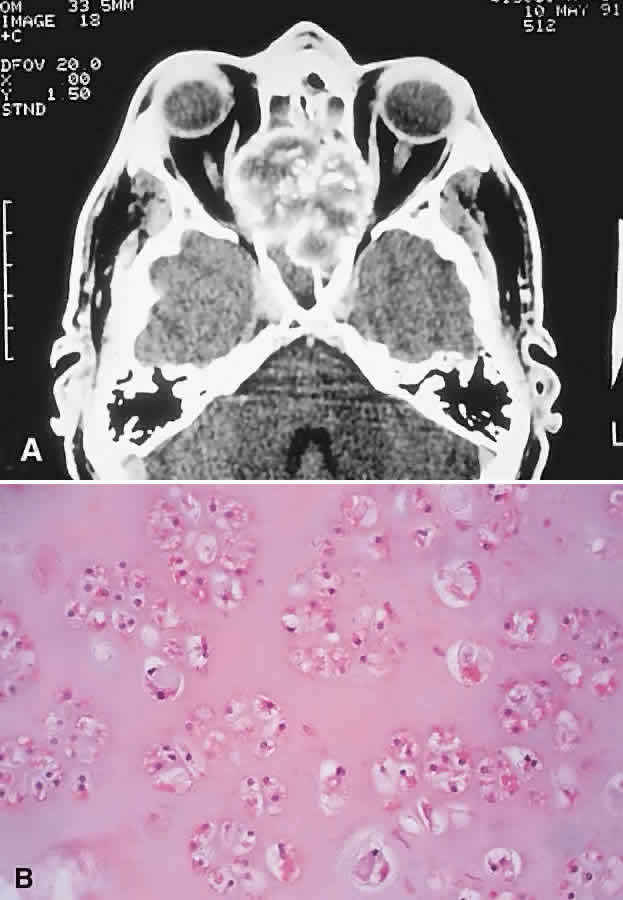

IMAGING. Chondrosarcomas appear as well-defined osteolytic lesions with stippled or mottled densities indicative of mineralization (Fig. 10). Higher-grade tumors tend to have irregular margins with nonuniform calcification in the form of amorphous cloudlike densities.125 The noncalcified regions show T1 signal intensities lower than or equal to gray matter on MRI. T2 signals are isointense to the cortex, and the masses usually display moderate enhancement.121,124,126,127

Fig. 10. This 46-year-old man with a history of midline chondrosarcoma resected 3 years previously presented with a right optic neuropathy. A. CT revealed recurrent tumor in the form of a heterogeneous mass involving both ethmoidal sinuses and orbit. Mottled areas of mineralization are apparent in the matrix of the lesion. B. The tumor was resected through an orbitocranial approach, and the histology revealed a grade 2 chondrosarcoma composed of hypercellular cartilage with lacunae containing binucleated chondrocytes (hematoxylin-eosin, × 50). He remains free of recurrence after 4 years.

HISTOPATHOLOGY. Grossly, the tissue is white to blue-gray, with a discernible lobular pattern. Histologically, there are irregular lobules of hypercellular cartilage with lacunae containing plump bi- or multinucleated chondrocytes, separated by fibrous stroma or reactive bony trabeculae. The stroma may be myxoid in areas and shows a wide variability in the amount of cellularity, atypia, and chondroid matrix, which has led to a grading system. The grades 1 through 3 appear to have some correlation with prognosis.119,121,128 This is manifest in tumors involving the orbit, which are mostly grades 1 or 2 and exhibit slow growth with a low incidence of metastasis.